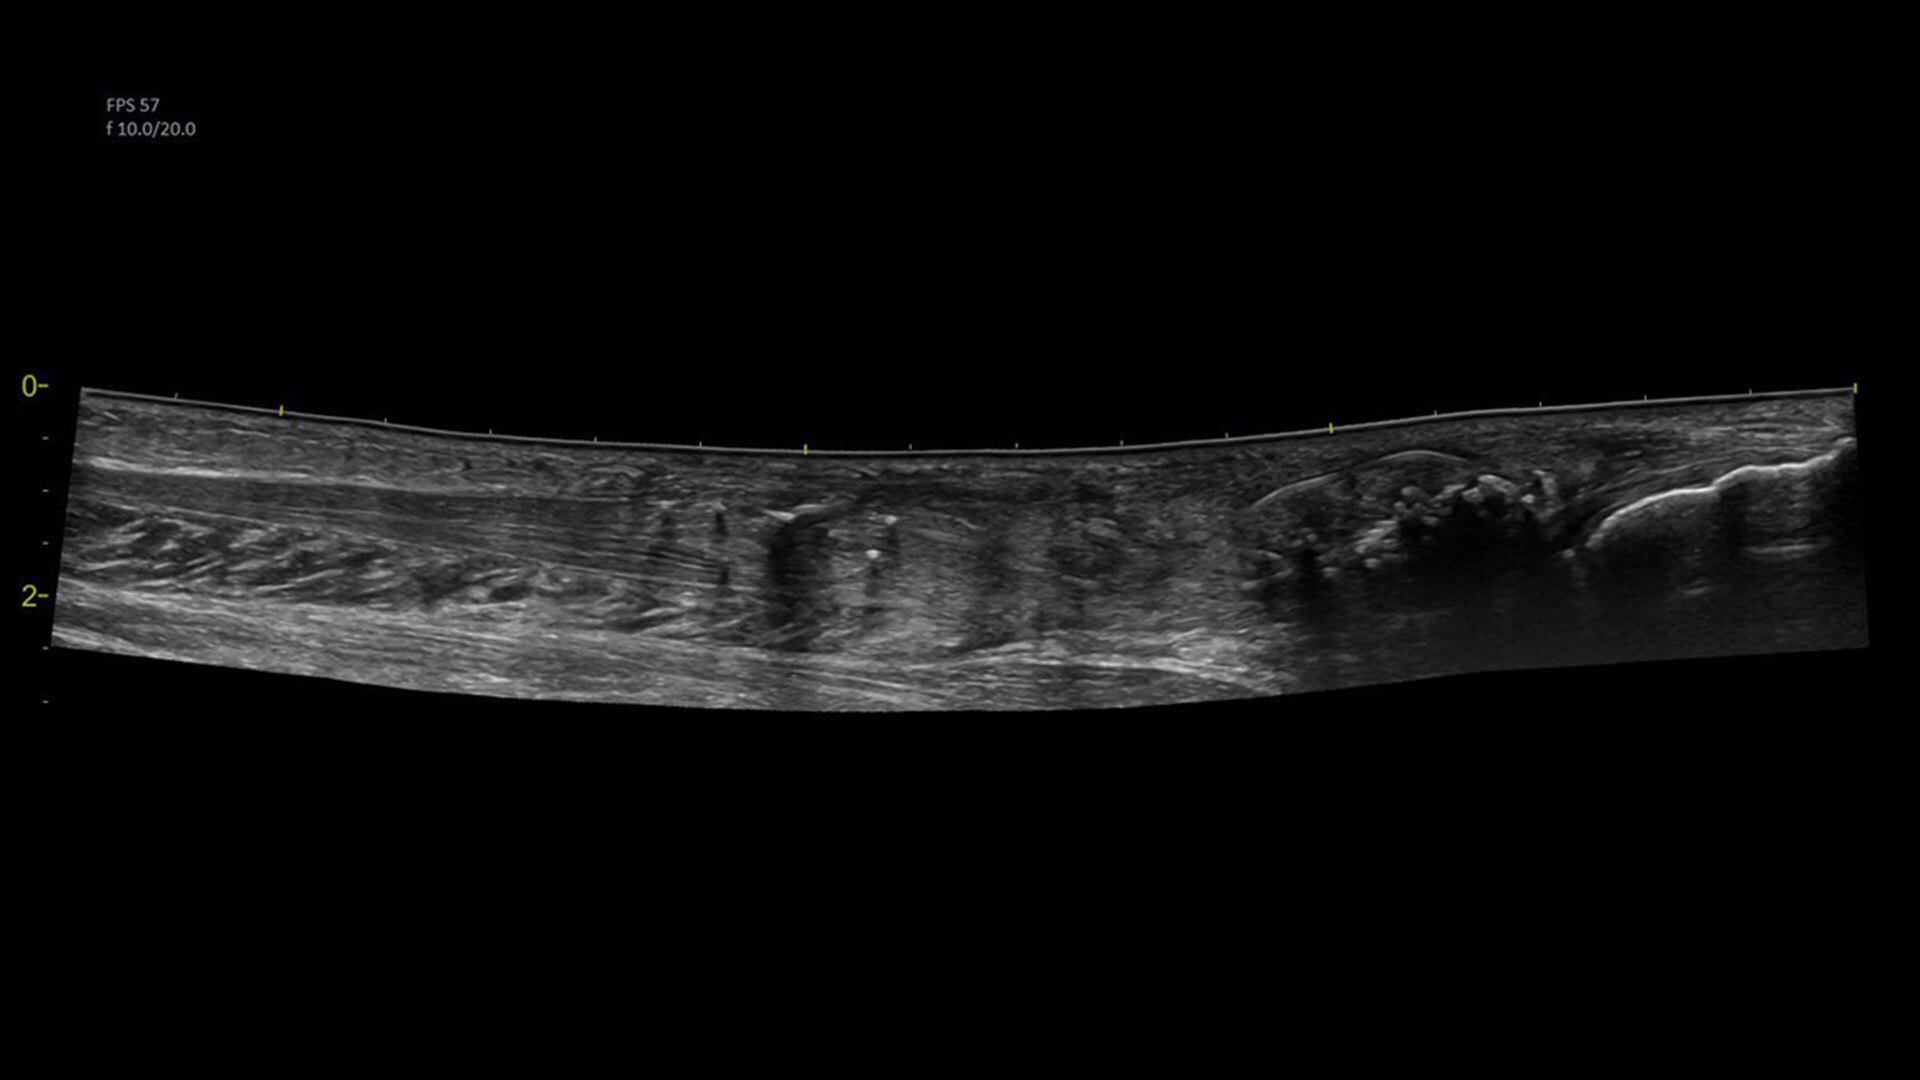

Visualize more anatomy in a single scan with Virtual Convex

This tool provides a wide field of view so users can visualize more large anatomy structures in a single scan.

Easily see the anatomy you need to see with Venue View

Supporting diagnostic confidence by constructing a panoramic image from individual frames, Venue View allows you to view up to 60cm of anatomy being scanned with anatomical relationships in one view.2